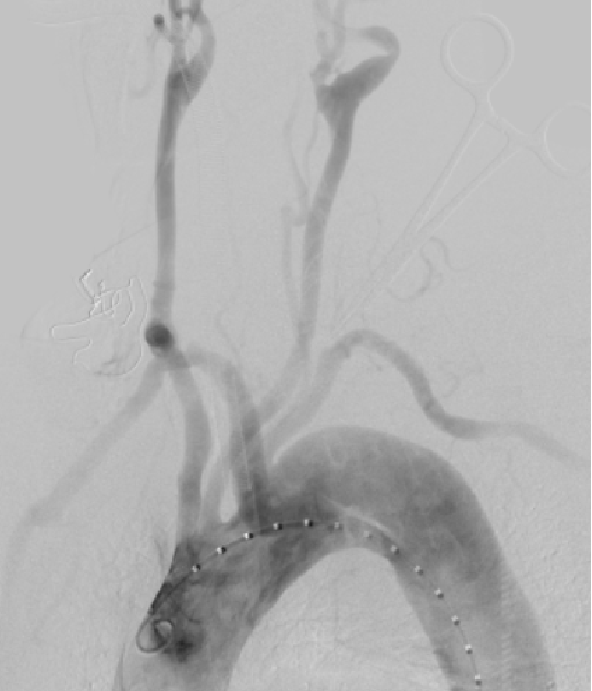

★平行支架技术(烟囱技术)

操作简便、手术时间短,适用于急诊、老年不耐受长时间手术患者及其他技术失败的中转或二次手术补救,小弯侧病变应用更多。但Ia型内漏风险高,即动脉壁、主体支架及分支支架形成的沟槽效应。目前,“裙边烟囱”技术在一定程度上解决了这一难题。

裙边烟囱技术